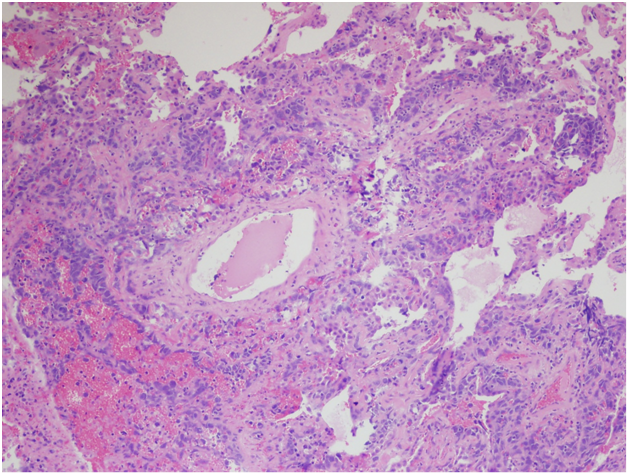

However, the wedge resection of the right lower lobe revealed angiosarcoma with lymphovascular invasion. This biopsy showed highly atypical and large malignant cells with increased mitoses (Figure 2A&2B). The immunohistochemical stains showed diffuse positivity for CD31, CD34, and vimentin (Figures 3A-3C). Stains for AE1/AE3 (Figure 3D), cam5.2, TTF-1, desmin, and OCT3/4 were negative. Along with the clinical history, a final diagnosis of angiosarcoma of the heart with metastases to the lungs was made.

The histology of this tumor has been described as irregular, anastomosing, vascular structures composed of endothelial-like cells, which can be either spindle-shaped or rounded and polygonal. Low grade lesions are composed of single- or multiple-layered vascular spaces while high grade lesions show sheets of poorly differentiated, pleomorphic cells.2 Immunohistochemical stain for CD31 is positive in 90% of PCAs and stain for FLI-1 in 100% of PCAs. Other commonly used positive stains include CD34, cytokeratins, vimentin and Factor VIII-related antigen,12 ranging from 35% to 74% positivity in PCAs described in the literature.